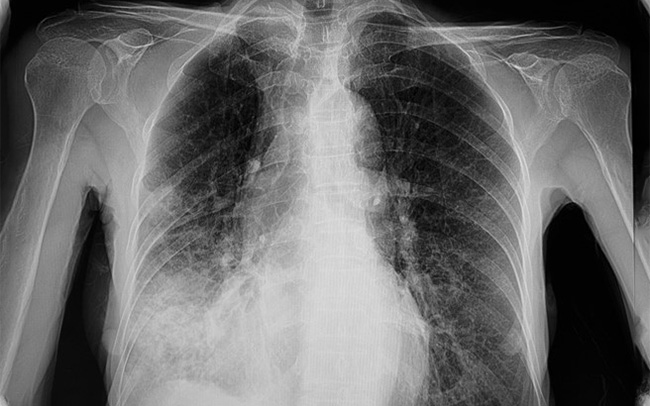

Pulmološki pregled nakon kovida obično uključuje razgovor sa pacijentom o njegovim simptomima, pregled i često dodatne dijagnostičke testove, kao što su spirometrija (test plućne funkcije) ili RTG pluća. U nekim slučajevima, mogu biti potrebni i složeniji testovi poput CT skeniranja pluća ili bronhoskopije. Jedan od ključnih alata u dijagnostici i praćenju pacijenata koji se oporavljaju od COVID-19 je RTG pluća. Infekcija kovidom može izazvati upalu i oštećenje plućnih tkiva, što se može videti na RTG snimcima. Zbog toga je ovaj test često ključni deo procene pulmologa.

Ključan deo pregleda predstavlja RTG pluća. Poznato je da COVID - 19 može izazvati značajne promene na plućima, uključujući upale i ožiljke, što se može videti na snimcima. Upravo oni mogu pomoći u velikoj meri pulmologu da oceni oporavak pacijenta i da identifikuje bilo kakve trajne probleme.